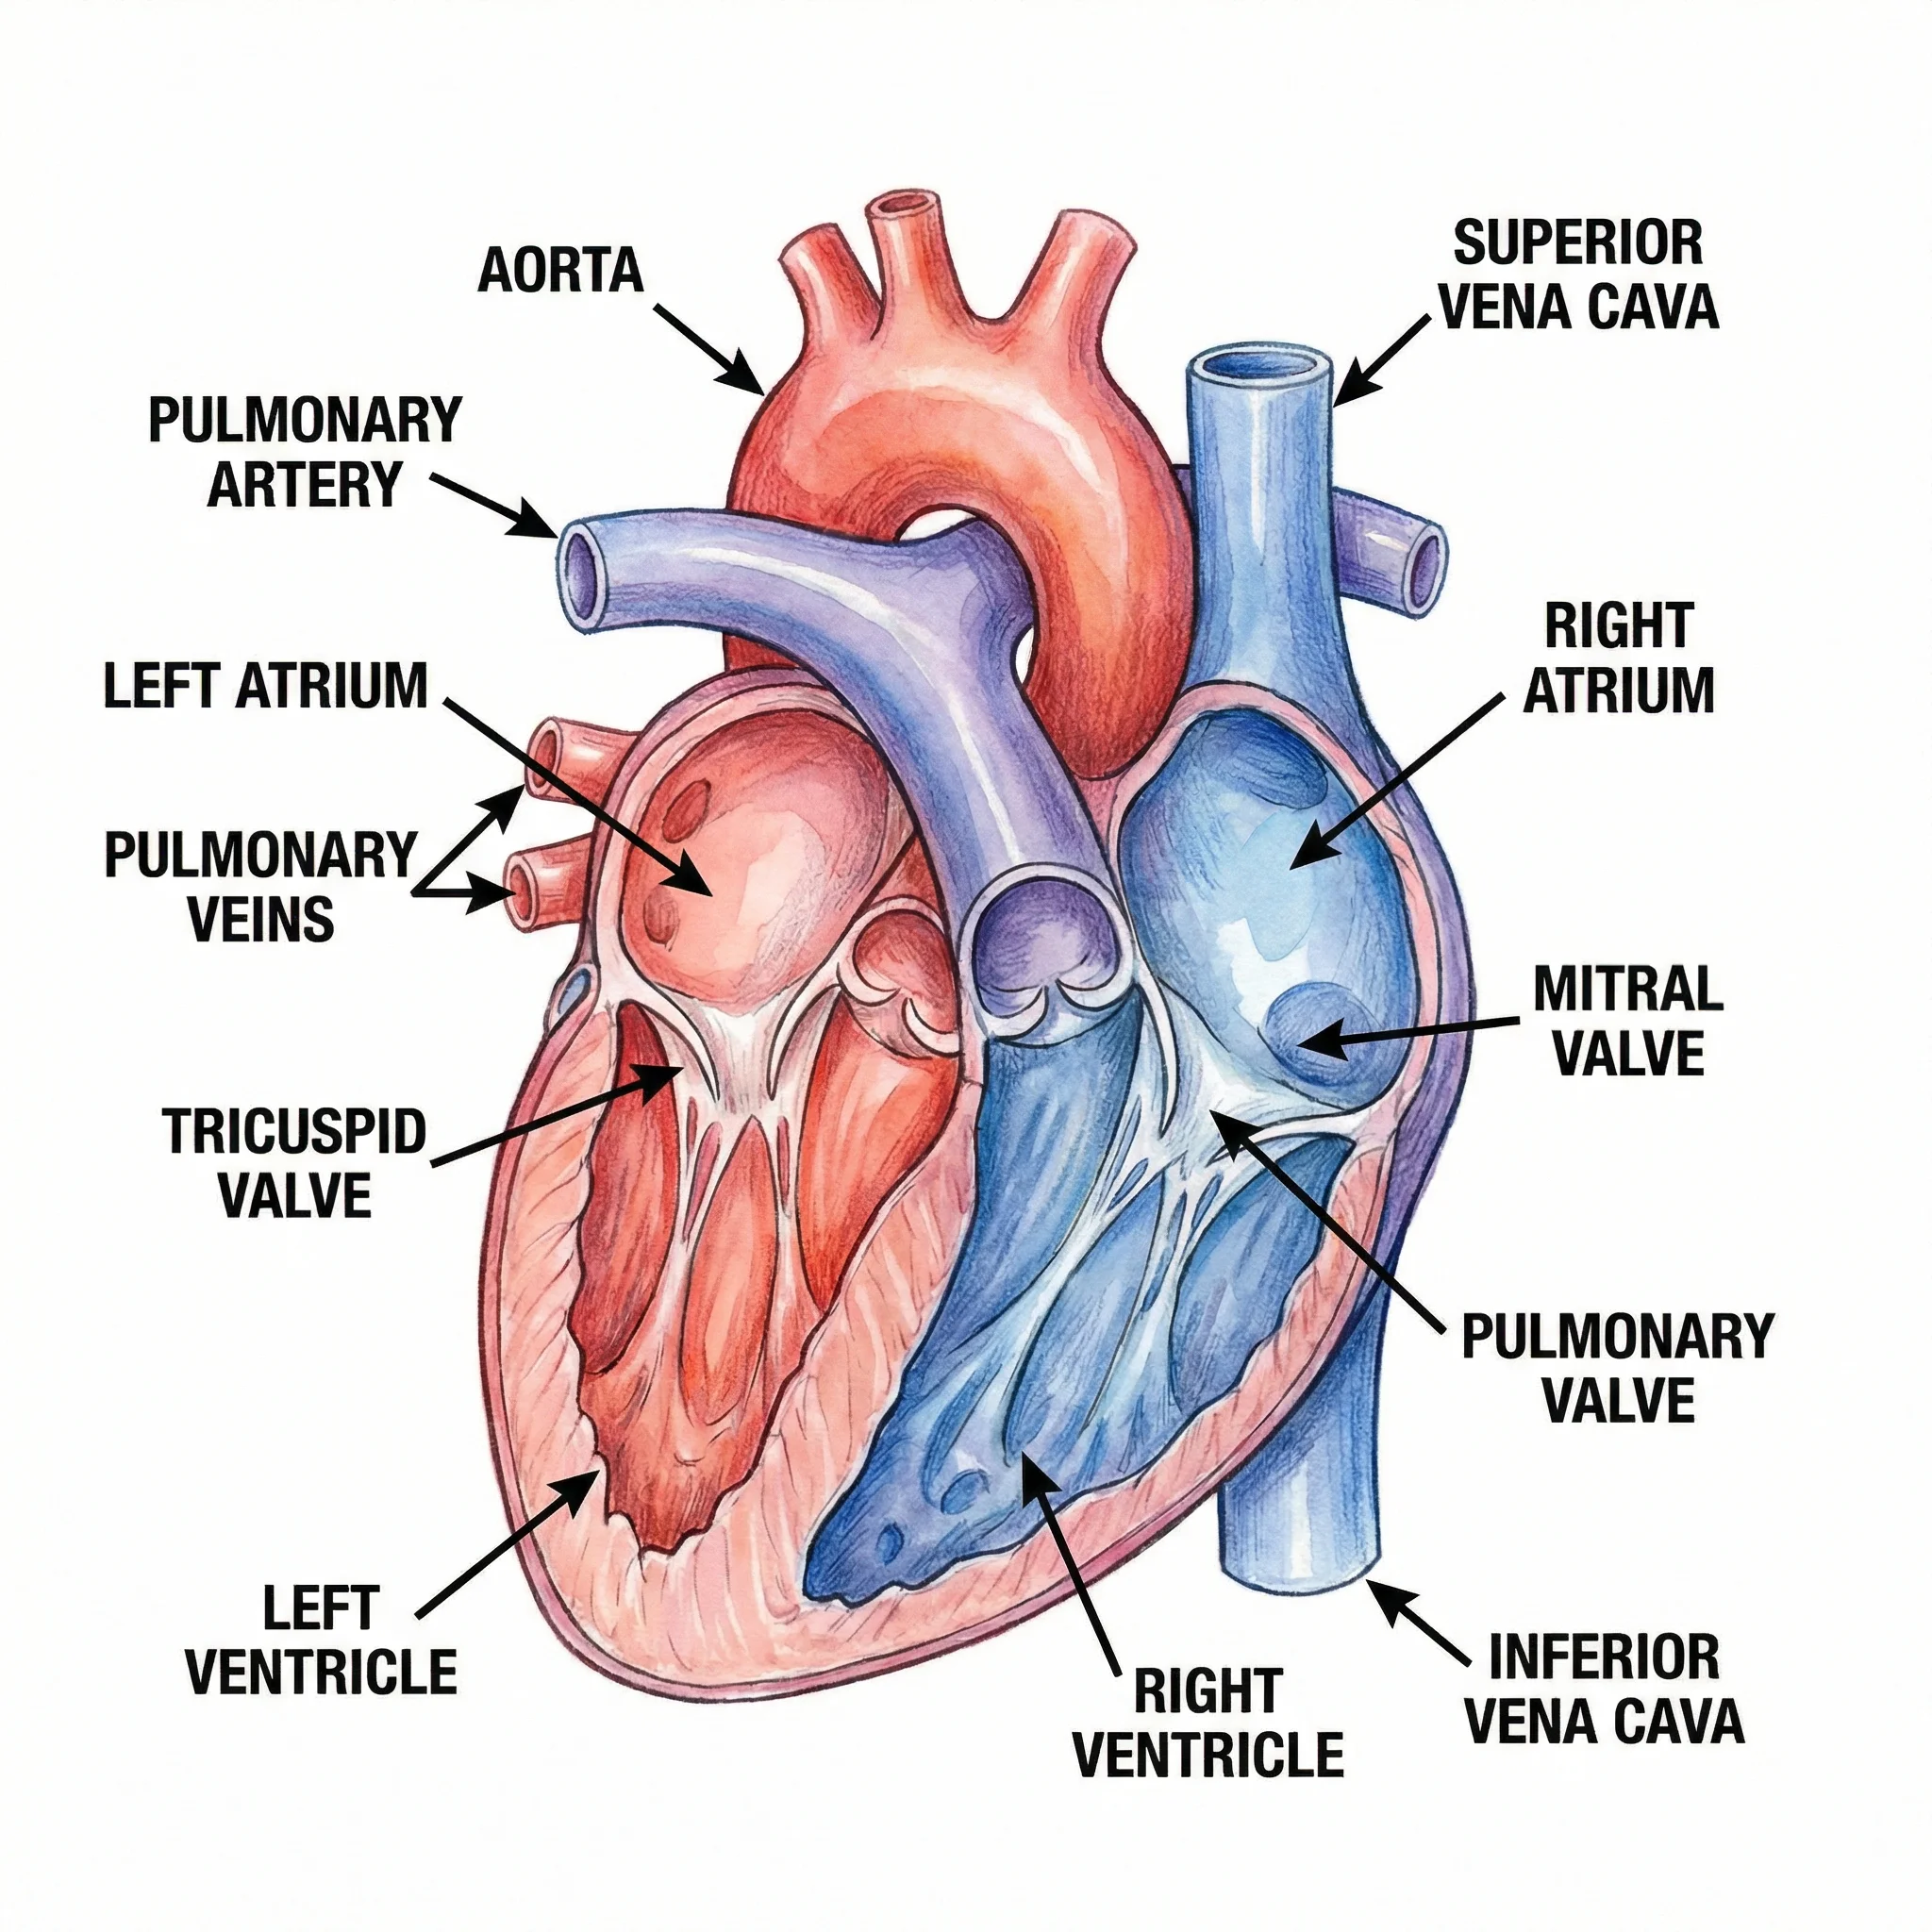

Medical

MedicalMedical Illustration Generator

Generate professional medical illustrations for healthcare education.